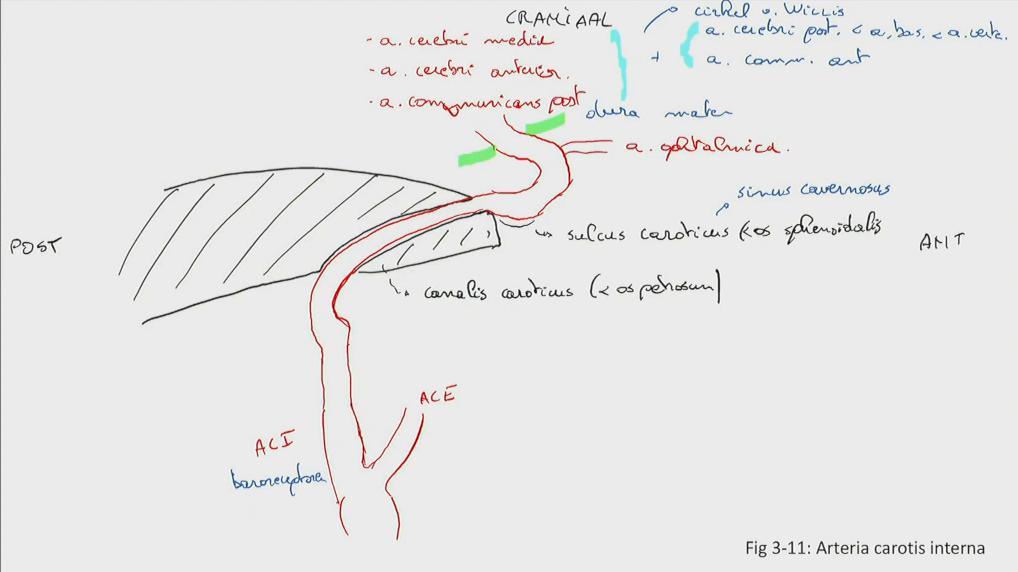

Fig 3.11: a. carotis interna

-

schedelbasis

-

a carotis communis

-

cirkel van Willis

details: zie neuro a vertebralis > a basilaris > a cerebri posterior a carotis interna > a cerebri media a carotis interna > a cerebri anterior a carotis interna > a communicans posterior a communicans anterior

|

|